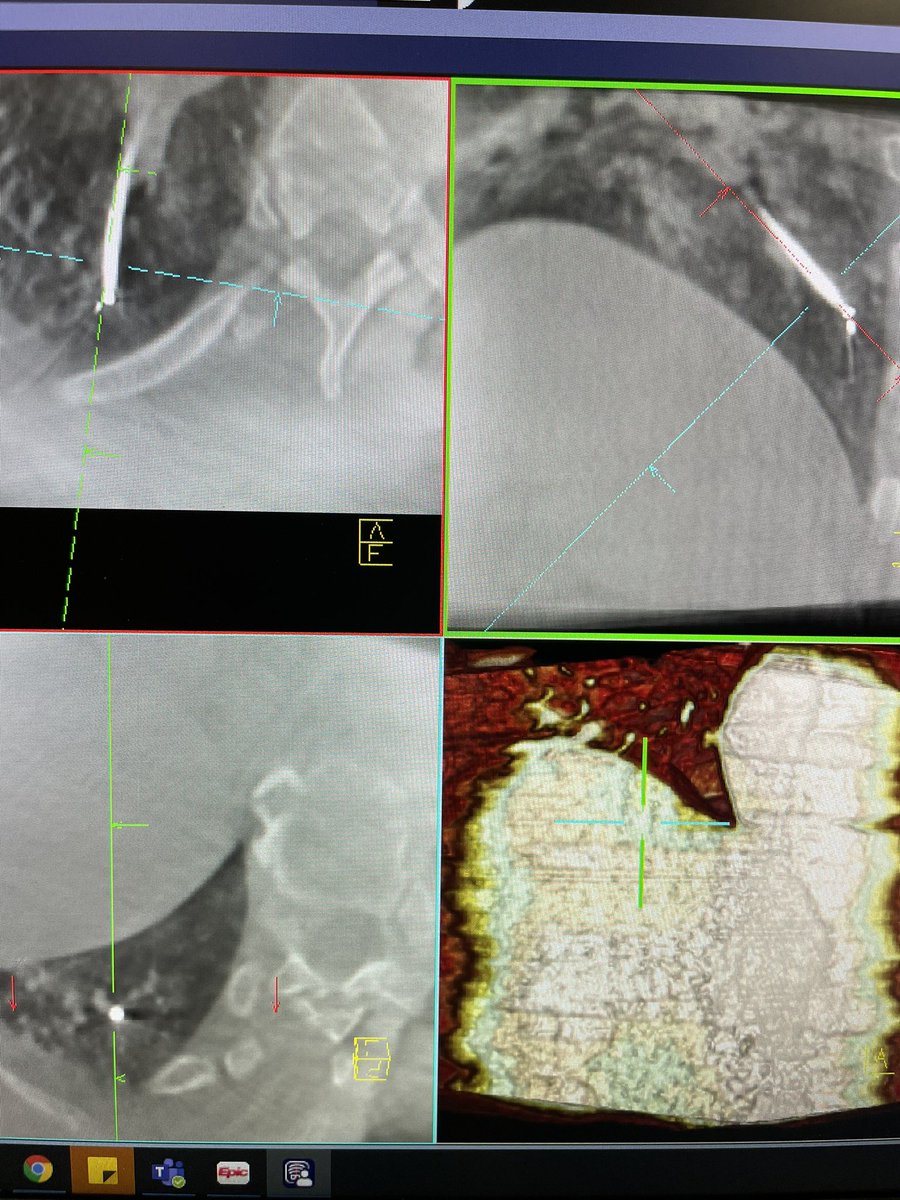

Ramsy Abdelghani, MD@Rabdelgh·

Cool case: 4.5mm partially solid PET-Avid LLL nodule. Used High PEEP/Tidal volume and wedged left side up to decrease dependent atelectasis. Navigated with Ion and adjusted with Philips CBCT. ROSE positive for Adenocarcinoma. Exciting times in lung cancer care! #ION #cbct

Growing LUL pleural based lesion with no airway leading to it and negative on IR biopsy. Was able to navigate close (within 2cm) to the lesion, biopsy, and adjust using CBCT. Positive for poorly differentiated carcinoma. I would have never tried this without CBCT and Robotics.